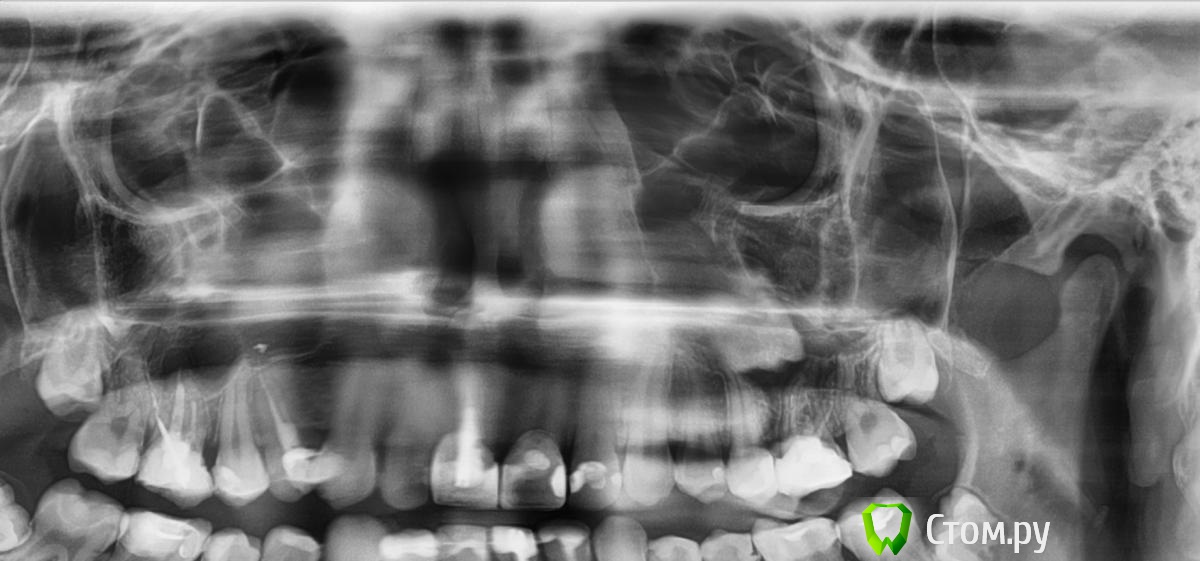

jm3300 Опубликовано 9 сентября, 2014 Автор Поделиться Опубликовано 9 сентября, 2014 кт пока не могу,с телp20140820_105219_0000.bmp Ссылка на комментарий

jm3300 Опубликовано 9 сентября, 2014 Автор Поделиться Опубликовано 9 сентября, 2014 в области 25,26 Ссылка на комментарий

АнтонТЛТ Опубликовано 9 сентября, 2014 Поделиться Опубликовано 9 сентября, 2014 (изменено) и срезы кт))оптг ужасного качества Изменено 9 сентября, 2014 пользователем АнтонТЛТ Ссылка на комментарий

DokDent Опубликовано 9 сентября, 2014 Поделиться Опубликовано 9 сентября, 2014 На точность изображения влияют многие факторы.Возможно это искажение изображения-такое образование на клкт было бы видно. "+" к докторам-оптг плохого качества- надо повторить. Ссылка на комментарий